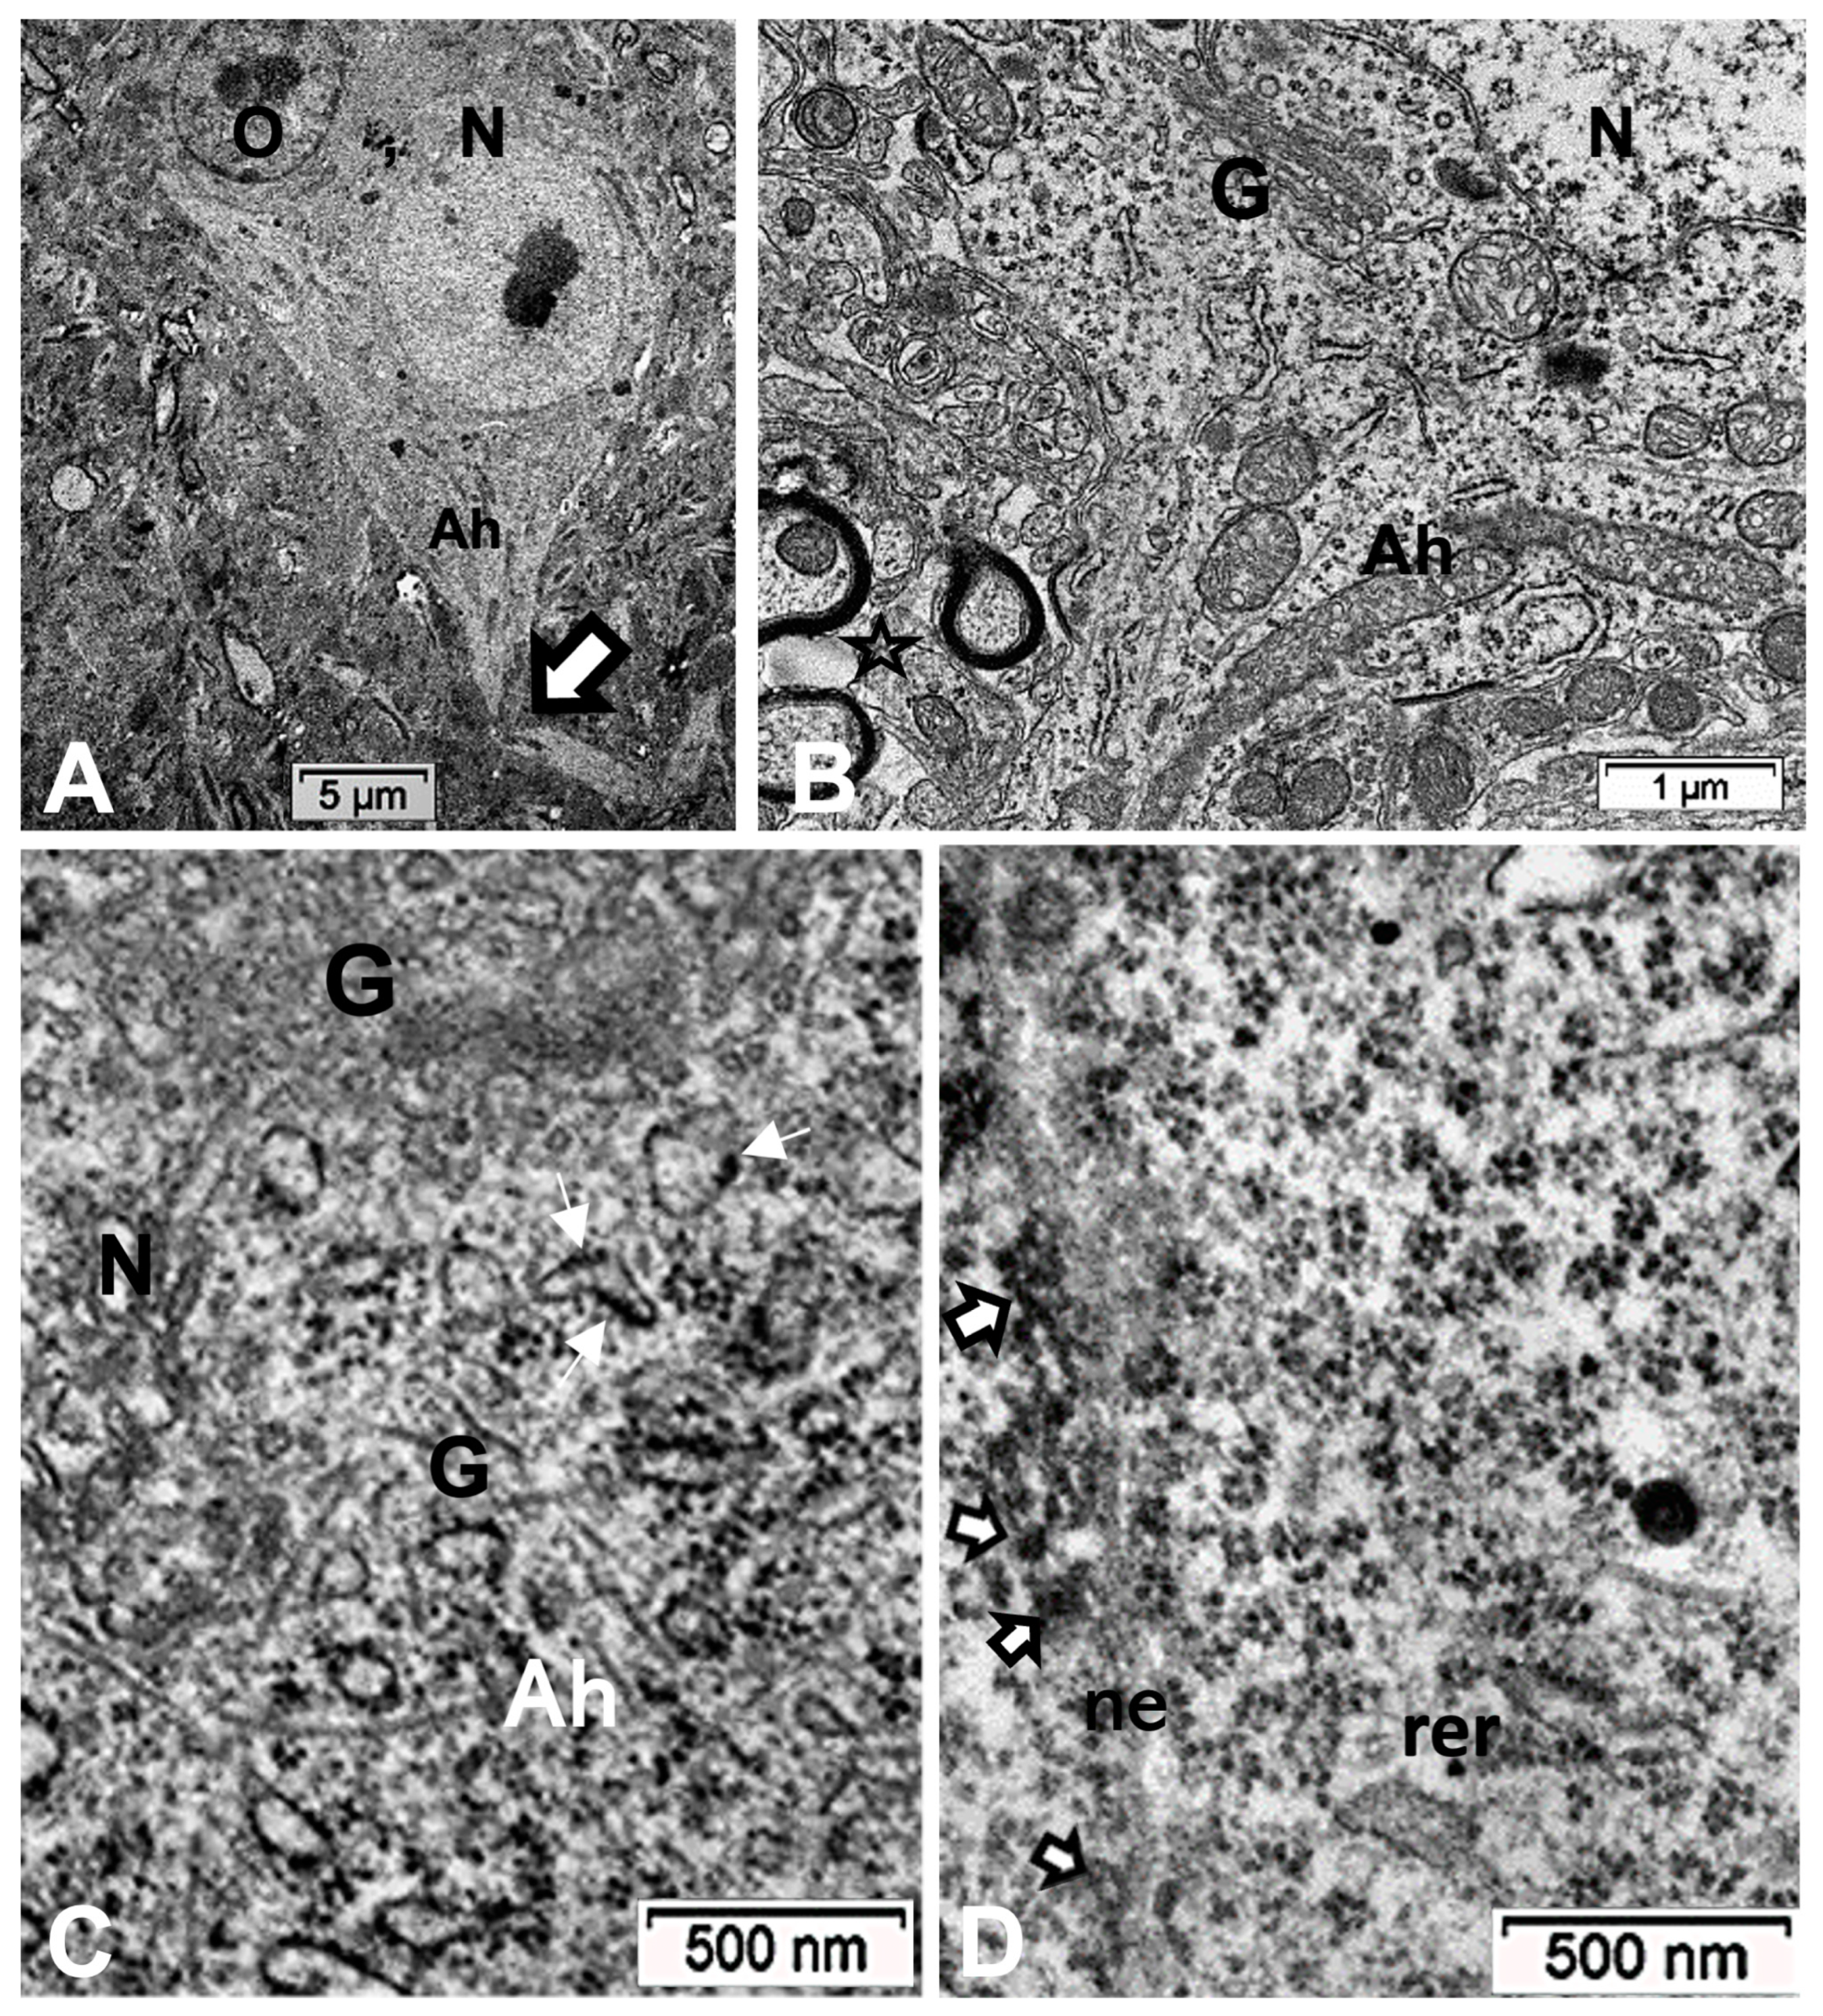

Figure 2 displays thalamus changes as a set of histology parasagittal sections of NN, HN, ODS 12 h and ODS 48 h murine brains, stained with Eriochrome C. Adjacent sections were used for MBP and ARL13b immunochemistry studies. As shown in Figure 2, of the parasagittal sample brain sections from each animal group, it is only in the ODS48h-treated mice where the thalamus reveals a clear, approximately 1–1.2 mm diameter-wide pale-stained posteroventral region. There, a regional thalamic myelinolysis is revealed by the loss in the Eriochrome staining and MBP immunoreactivity (asterisk in Figure 2) while, in the other treatment groups, no obvious difference in overall myelin staining intensities was observed. In the ODS48h, thalamic ventral posterolateral (VPL) and ventral posteromedial (VPM) relay nuclei to contain the worst demyelination region, and a typical Eriochrome hue background is recovered within a 30–50 µm narrow distance away from the outskirts of the 200–250 µm damaged core zone, indicating there is a somewhat blurred degradation limit for the damaged brain region, revealed with a distinctive paler contrast after chronic hyponatremia compared with the other brain treatment groups sampled.

2.5. ARL13B Label in ODS48h: LM and TEM: A Primary Cilium Emergence

The thalamic neurons located adjacent but at less than 100 µm distal from the necrotic core ODS, as seen in Figure 8A–E, and more clearly in Figure 9, can be recognized from their shape, using LM, as a large pale nucleus with indent(s) that reveal an evident stained nucleolus and, with TEM, the same highly contrasted, large nucleolus shows large amounts of accumulated granular transcripts (as granular component) accompanying the dense and fine fibrillar components of the chromatin distributed throughout the very active nucleoplasm (Figure 9A, Figure 10A, Figure 11A and Figure A2). At first glimpse, the adjacent neuropil and the satellite oligodendrocytes appear typically located attached to neurons as satellites but, with TEM scrutiny, these were mostly damaged by ODS cell stress and are surrounded by large neuropil intercellular spaces throughout and possess other cells’ and myelin remnants, implicated after leakage of blood fluids, plasma with serum, contributed via the small regional necrotic cells to the archetypal term of ‘liquefaction necrosis’. However, within this ODS damaged zone outskirts, among some degraded and corpses of neuropil, resilient neurons found in the outskirt region were marked by large euchromatic nuclei and active nucleolus; they showed numerous ribonucleoproteins but also reveal through their fine structure that they possess delicate but clear-cut primary cilia (Figure 10A,B). Each cilium length ranged from 4.5 to 6.0 µm long and width from 0.2 to 0.25 µm that is filled with a core of granular cytoplasm and microtubules. The example illustrated shows its transition zone cell attachment consisting of a narrow transition segment or ‘neck’ of about 0.15 µm in width, that is tied by basal fibrillar materials, and forms a ciliary pocket or cove-like space of the plasma membrane. Within the neuroplasm, obscured by numerous ribosomes, a microtubule fascicle and other subcellular filaments can be barely seen originating from the adjacent perikaryal region and reaching the basal side of the primary cilium whose random sections constitute a sort of ‘hub’ region, probably endowed by a centriolar piece structure in some other ultrathin section. In Figure 10A–C, adjacent to the primary cilium, one can note filopodia-like extensions, as these could also be relevant to this rejuvenated change associated with cell resilience (Figure 10C). Other neurons of the same region (Figure 8D,E), at low magnification, bear an axon hillock that becomes like a funnel, similar to the neurons, and more distally located away from the core ODS damages, as shown in Figure 11, Figure 12, Figure 13, Figure 14 and Figure A2, displaying axon hillocks and an axon initial segment without any ciliation. Underlined by ocher yellow (Figure 12A) and enlarged in Figure 12B, the Golgi apparatus saccules characteristically erupt in numerous small vesicles (50–70 nm diam) that accompany ribonucleoprotein particles (mainly RNAs), revealing swirled ribbons of polysomes in places. Vesicles and particles appear to redistribute into the AIS, showing as an initial squeezed cylindric shape aligning the entered neurotubules into a paraxial to parallel orientation congested by one or more long, twisted mitochondrion. Both mitochondria profiles and inner neurolemma leaflet can be decorated by small round to elongated vesicles while the outer leaflet has typically no myelin. However, some synaptic contacts are noted amongst end-feet profiles of astrocytes, recognized by their highly contrasted granules of glycogen content (Figure 12A,B).